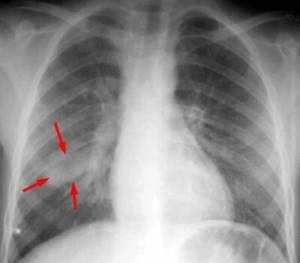

Рентгенодиагностика бронхопневмонии: Советы и примеры

Раздел: Альбом открытий